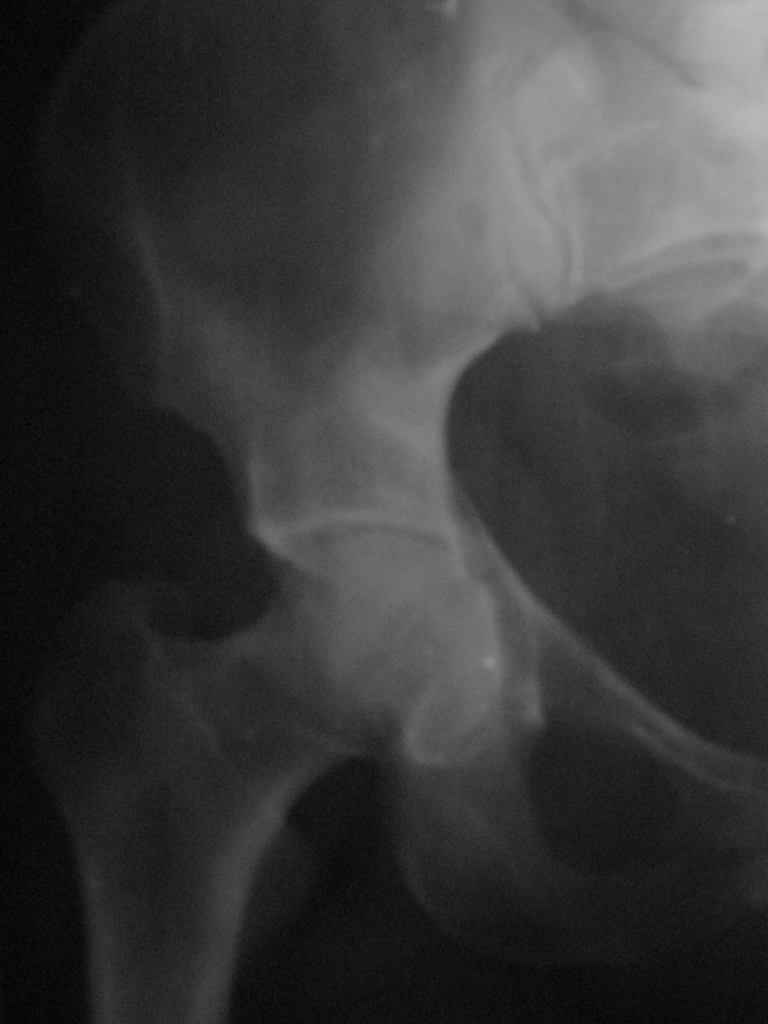

Женщина,58 лет, после ДТП 6 суток. Первично повреждение расценено как переломы ветвей

лонной кости.

сломался. Прилагаю стандартные снимки вертлужки. У меня следующие вопросы к коллегам: 1.

Правильно ли рассценивать это повреждение как Т-образный перелом вертлужнй впадины? 2.

Можно ли добиться анатомической репозиции поверхности вертлужной впадины скелетным

вытяжением в данном случае, если нет, что будет этому препятствовать? 3. Если смещение

останется таким как сейчас, через какое время появится необходимость эндопротезирования

(по вашему опыту)? Спасибо.